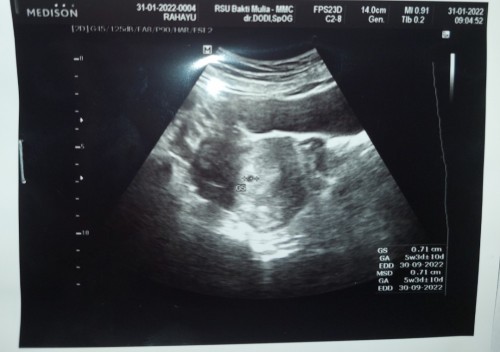

Assalamualaikum bun..bun disini ada gak yang lagi hamil 4weeks udah USG kayak aku..kalau ada komen dong sekalian hasil foto USG nya bunda..hpht 17 nov 2021 tapi UK aku gak sesuai karena haid ku gak teratur alias dibawah 21 hari siklusku..jadi dokter memutuskan ikut usia kehamilan dari USG☝🏻😍🤲🏻MASYAALLAH.. #seriusnanya #bantusharing #ingintahu #MYBABY #number2